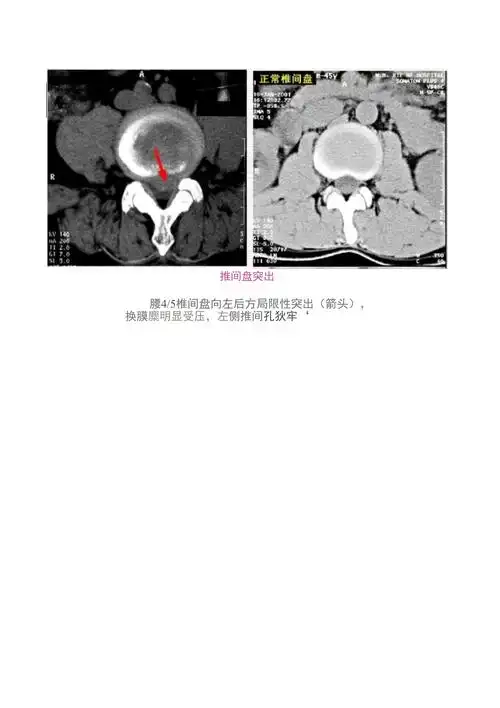

腰椎ct示:腰4-5椎间盘突出(左旁中央型),腰5-骶1椎间盘突出(中央型)